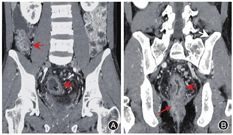

与结肠型CD相比,UC患者的病变更多表现为连续性分布(80%比57.5%,P = 0.03)、肠壁呈环周均匀性增厚(77.5%比47.5%,P = 0.006),较少出现肠周炎性渗出(20.0%比67.5%,P<0.001)及肛瘘(10.0%比57.5%,P<0.001),差异均有统计学意义。结肠型CD病变肠壁厚度大于UC患者[(9.5 ± 3.4) mm比(8.1 ± 2.2) mm,P = 0.024],更多表现为不同部位的严重程度不一致(75.0%比45.0%,P = 0.006),差异均有统计学意义,见图1,图2,图3,图4。两组患者其余影像学特征差异无统计学意义(P均>0.05)。见表3。

本研究中,尽管两组患者的病变部位多发生于远端结肠,但升结肠受累在结肠型CD患者中更常见,升结肠受累也是多因素回归模型中的有效预测因子。笔者猜测可能是由于UC为倒灌性结肠炎,病变初始发生在远端结直肠,本研究纳入人群为初诊的患者,广泛结肠受累的人群较少。直肠受累多见于UC,但本研究中55% CD患者也伴有直肠病变,两组差异无统计学意义。一项关于北美人群的流行病学显示,50%结肠受累的CD患者伴有直肠受累,与本研究结果一致[14]。在累及结直肠病变部位的数目方面,两组患者差异无统计学意义,提示两者均可同时出现多处结直肠病变。

与UC相比,结肠型CD更多表现为病变节段性分布、非对称性肠壁增厚,厚度多厚于UC,肠周炎性渗出及肛瘘也更加常见,多变量回归模型也提示肠周炎性渗出、肛瘘是诊断结肠型CD的有效预测因子。多节段性病变是CD的典型影像学表现,而UC患者更多表现为病变连续性分布,与既往报道的一致[15]。另外,结肠型CD患者以非对称性肠壁增厚为主,提示即使位于同一部位的病变,CD患者仍具有跳跃性的趋势,从而表现为影像学上单一节段的肠壁厚薄不均匀。这同样解释了结肠型CD患者在不同部位表现为炎症反应程度不一致的可能原因,而UC患者则更常出现结肠病变相一致的影像学表现。然而,进一步多因素回归分析显示,节段性病变与非对称病变并不能作为诊断结肠型CD的独立预测因子。在肠壁厚度上,结肠型CD患者厚于UC患者,我们认为这与CD表现为累及肠壁全层的透壁性炎症相关,除黏膜层受累之外,黏膜下层炎性水肿也常常同时出现,更有甚者累及肌层之外。而UC仅累及肠壁的黏膜层,病变浸润深度往往表浅,造成了两者影像学上的厚度差异,虽然多因素回归模型显示肠壁增厚没有显著差异(P = 0.051),但肠壁厚度越大,诊断结肠型CD仍具一定的优势比。Ellrichmann等[16]通过超声内镜比较UC与CD的结肠病变厚度,证实了CD黏膜下层厚度高于UC(P = 0.0001),CD平均肠壁厚度稍高于UC,但两者之间差异无统计学意义(P = 0.06)。本研究中,结肠型CD常伴有肠周炎性渗出,而UC患者少见,这或许依赖于两者在病理上累及肠壁的深度及层次有所不同,从而导致继发肠周炎性渗出改变的差异。肠周炎性渗出的出现明显提高了诊断结肠型CD的价值,这也是多因素回归模型中诊断结肠型CD的重要预测因子。另外,结肠型CD患者有50%以上会合并肛瘘,而UC少见,肛瘘是本研究中回归模型的关键预测因子,具有高优势比,其中的具体机制尚不明确,但肛瘘的出现对结肠型CD的诊断具有重要的参考价值。这也提示我们,IBD患者在行腹部检查时,放射医师应尽量覆盖肛管的扫描,这将进一步有助于临床诊断。